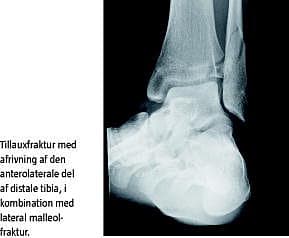

Skaden opstod i forbindelse med en sneboldkamp, da patienten gled på iset underlag og forvred det venstre ankelled. Patienten kunne efterfølgende ikke støtte på foden, og der opstod en stor hævelse omkring laterale malleol. Ved palpation var der direkte og indirekte ømhed af laterale malleol samt ti centimeter op langs distale fibula. Der var ingen ømhed eller hævelse ved mediale malleol. Ved hjælp af røntgen påviste man en udislokeret spiralfraktur i den laterale malleol samt et dislokeret ledbærende fragment anterolateralt i distale tibia svarende til en Tillauxfraktur. Da frakturerne var meget tydelige at se på røntgen, blev der ikke foretaget en computertomografi (CT). Patienten blev opereret dagen efter uheldet med anbringelse af osteosyntese i anatomisk stilling. Man fandt Tillauxfrakturen helt løs og displaceret en centimeter fremad. Der blev indsat to lag skruer i laterale malleol samt en spongiosaskrue i Tillauxfragmentet. Patienten blev behandlet med ROM walker i seks uger og måtte kun skyggestøtte de første tre uger. Bruddene helede op uden komplikationer, og patienten opnåede fuldt normal funktion af ankelleddet.

Ved Tillauxfrakturer er det vigtigt med præcis diagnosticering af dislokationsgraden [2]. Der skal altid foretages almindelig røntgen med antero-posterior, lateral og skråprojektion, og ved tvivl om dislokationsgraden skal der gennemføres CT med 3D-rekonstruktioner, som er bedre til at fremstille forskydninger på over to millimeter [4]. Det er vigtigt med CT, da grænsen mellem konservativ og operativ behandling som regel går ved en dislokation på over to millimeter [4]. Hvis frakturen ikke reponeres eksakt, kan der udvikles sekundær artrose med smerter, ledstivhed, varusdeformitet samt mangelfuld lukning af epifysen [2].